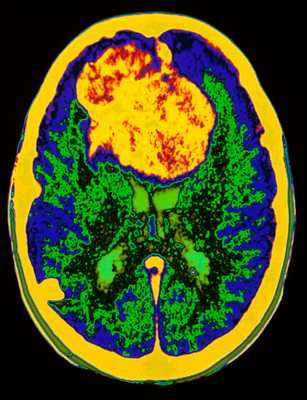

МРТ головного мозга. Аксиальная Т2-взвешенная МРТ. Цветовая обработка изображения. Опухоль мозга.

При дифференциальной диагностике опухолей головного мозга надо учитывать многие факторы включая эпидемиологические и диагностические. Золотым стандартом их выявления служит МРТ головного мозга. Многие центры МРТ СПб берутся за эту задачу, но мы рекомендуем Вам обследоваться именно у нас. При МРТ в СПб в дифференциальной диагностике опухолей в высоком поле и на открытом МРТ мы учитываем многие признаки, включая следующие: